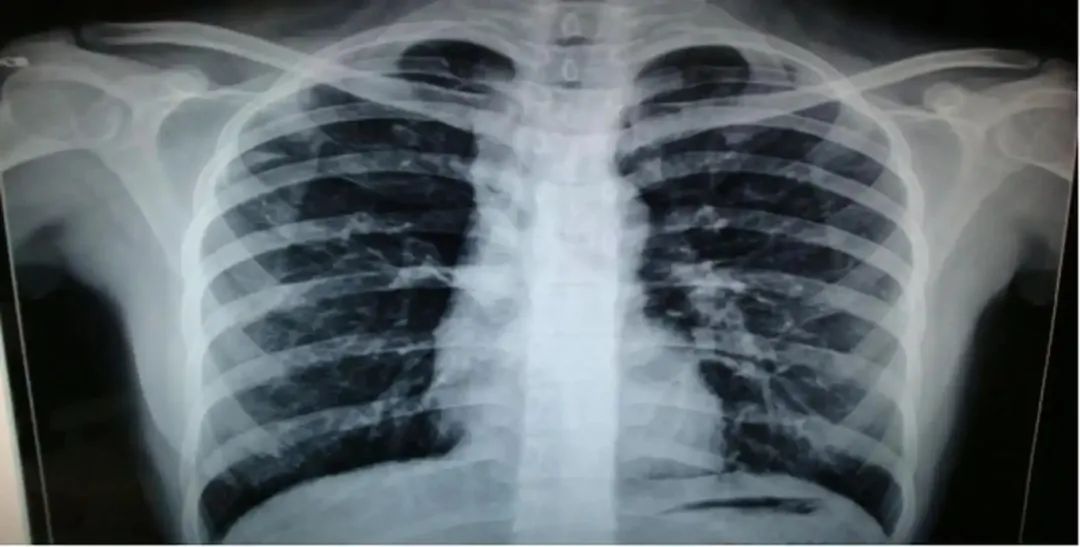

“您的肺上不仅有结节,还有陈旧性病变。”

"王先生,CT显示,您的肺中有结节,且有肺结节钙化灶。"